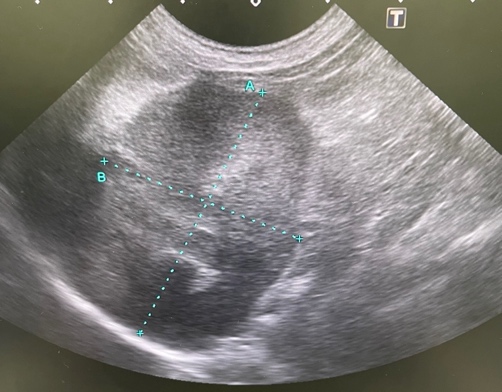

腎臓腫瘍

血尿や腹部の腫れ、腹部の不快感などを示します。

犬では腺癌が最も多く認められる腫瘍で、猫ではリンパ腫の発生が多い。

片側の腎臓腫瘍で、転移性所見のない症例では外科的摘出手術が適応になります。